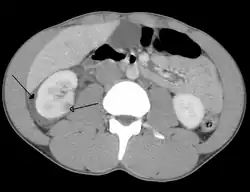

| Abdominal trauma resulting in a right kidney contusion (open arrow) and blood surrounding the kidney (closed arrow) as seen on CT | |

Kidneys

The kidneys may also be injured; they are somewhat but not completely protected by the ribs.[6] Kidney lacerations and contusions may also occur.[13] Kidney injury, a common finding in children with blunt abdominal trauma, may be associated with bloody urine.[13] Kidney lacerations may be associated with urinoma or leakage of urine into the abdomen.[4] A shattered kidney is one with multiple lacerations and an associated fragmentation of the kidney tissue.[4]